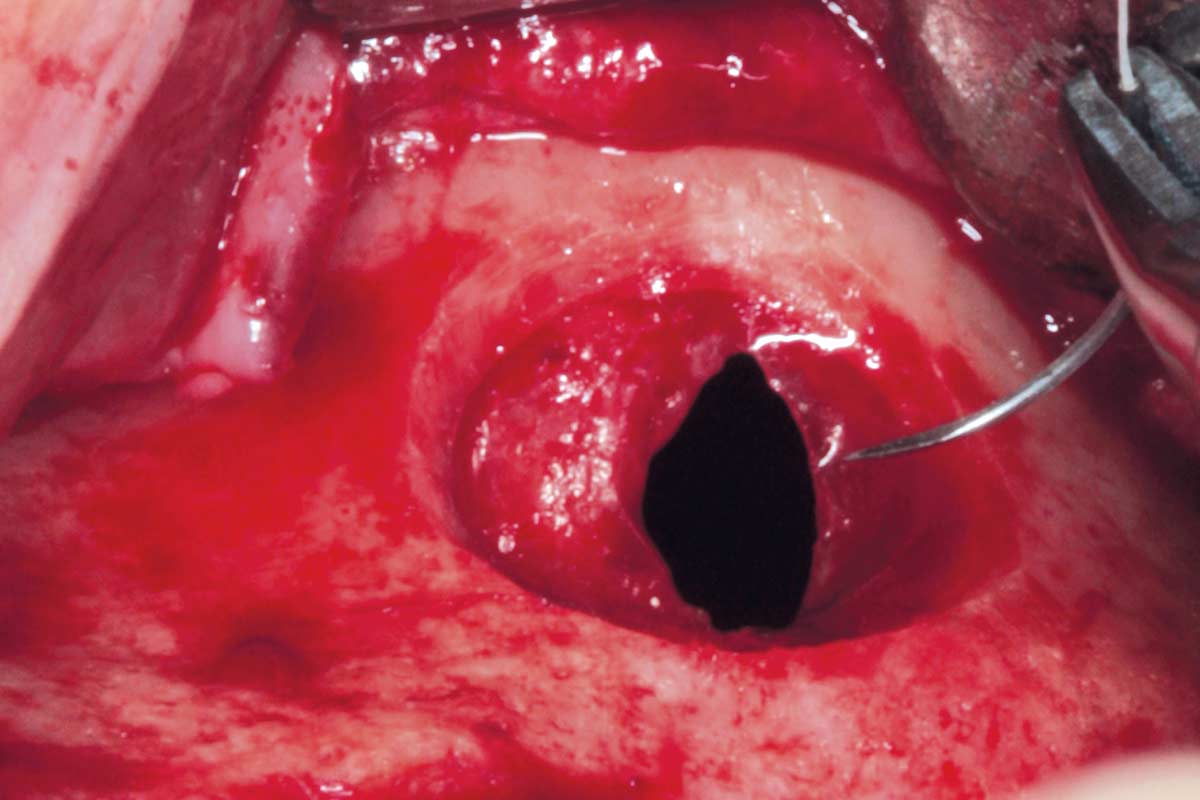

06/35 - Aspiration of the cystic contentsMaxillary sinus cyst removal using the Crocodile Technique and subsequent lateral sinus lift - Dres. C. Scognamiglio and A. Perucchi

07/35 - Removal of the cyst from the sinusMaxillary sinus cyst removal using the Crocodile Technique and subsequent lateral sinus lift - Dres. C. Scognamiglio and A. Perucchi